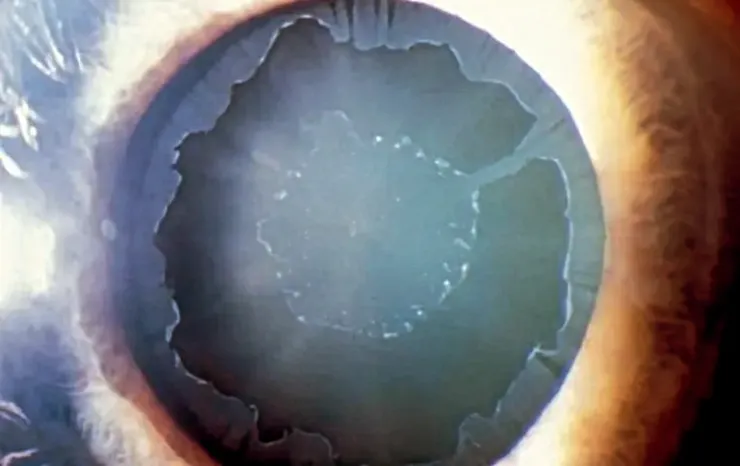

PXF是導致白內障手術中小瞳孔的常見原因,這種情況和年齡增長及遺傳有關。PXF不僅增加了白內障的風險,還常伴隨著晶狀體懸韌帶的脆弱,增加手術難度。

圖片為一PXF病人的白內障照片。[credit: Eyewiki]